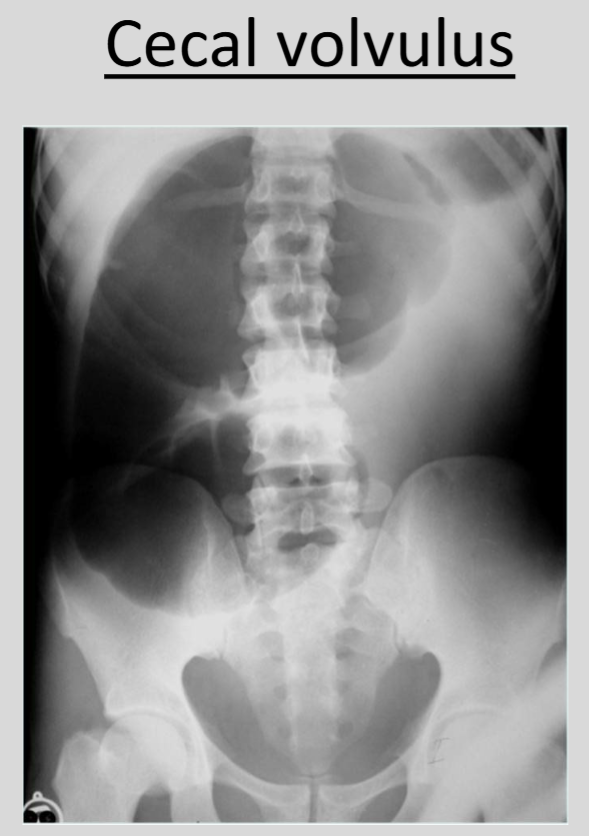

What is the significance of the 'C sign' in medical imaging?

The 'c sign’ is a cecal volvulus, a condition in which the cecum twists around itself or its mesentery